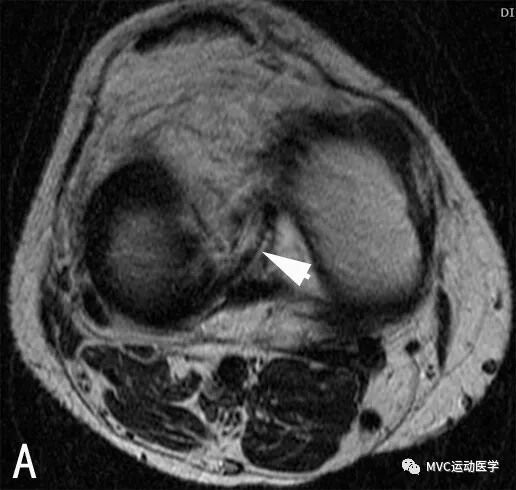

十、假性桶柄样撕裂

常出现在外侧半月板后角的冠状扫描层面上,内侧半月板极少出现此情况。扫描层面同时包括外侧半月板体部及半月板后角,易误诊为桶柄样撕裂,在膝关节外旋时更易出现。结合矢状位相可排除桶柄样撕裂。

A:冠状位MRI,箭头所指为外侧半月板后角,易误诊为桶柄裂;

B:按照图中虚线所示的位置进行MRI扫描时,会出现假性桶柄样撕裂的情况